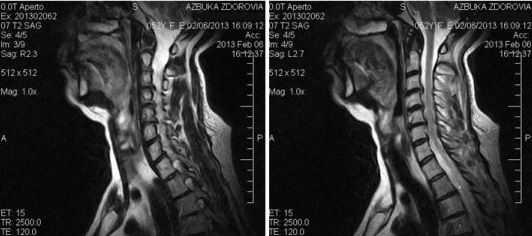

(Слева) Рентгенография шейного отдела позвоночника в прямой проекции: протезы дисков ProDisc-C на двух уровнях . Подобные вмешательства позволяют сохранить практически нормальную подвижность обоих оперированных сегментов и не приводят к ограничению подвижности смежных сегментов. Это дает основания полагать, что подобные многоуровневые ТЗШД могут быть более предпочтительными, чем спондилодезы.

(Справа) Рентгенография в боковой проекции после двухуровневого ТЗШД протезами ProDisc-С. Эти полусвязанные металл-полиэтиленовые протезы позволяют сохранить подвижность оперированного сегмента, высоту соответствующих межпозвонковых отверстий и сагиттальный баланс позвоночника. Ротационная подвижность между компонентами протеза в ряде случаев может приводить к биомеханической перегрузке дугоотростчатых суставов.

(Слева) Рентгенография шейного отдела позвоночника: протез межпозвонкового диска Bryan, состоящий из двух имеющих форму раковин [моллюсков] замыкательных пластинок, изготовленных из титана с пористым покрытием, и поликарбонат-полиэтиленового вкладыша. Этот протез отличается эластичными и амортизационными свойствами, обеспечивая свободные движения на уровне оперированного сегмента. Возможные осложнения включают переднюю или заднюю дислокацию компонентов протеза, кифотическую деформацию замыкательных пластинок и ограничение движений.

(Справа) Сагиттальный срез, Т1-ВИ, пациент с протезом Bryan межпозвонкового диска С5-С6. Протез характеризуется минимально выраженными артефактами магнитной восприимчивости.

(Слева) Рентгенография шейного отдела позвоночника в боковой проекции: протез межпозвонкового диска Prestige LP. Это титан-керамический протез с шаровидной парой трения. Замыкательные пластинки протеза фиксируются к телам позвонков винтами. Кроме того, они имеют пористое титановое напыление, обеспечивающее возможность интеграции с костью и стабильной фиксации компонентов протеза.

(Справа) Сагиттальный КТ-срез: протез межпозвонкового диска Prestige LP с металл-металлической парой трения. Протез обеспечивает возможность смещения в сагиттальной плоскости до 2 мм. КТ может быть информативна в отношении диагностики оссификации паравертебральных тканей.

(Слева) На сагиттальный срез, Т2-ВИ: грыжа диска С5-С6. Согласно современным литературным данным, ТЗШД-это вариант хирургического лечения шейной миелопатии у пациентов молодого возраста с центральными грыжами диска без выраженных дегенеративных изменений диска и дугоотростчатых суставов на уровне этого сегмента.

(Справа) Рентгенография шейного отдела позвоночника в боковой проекции: протез межпозвонкового диска ProDisc-C. Протез состоит из двух кобальт-хромовых замыкательных пластинок, снабженных центральными килями для фиксации в телах позвонков, и блокирующегося вкладыша из ультравысокомолекулярного полиэтилена, образующего с замыкательными пластинками шаровидное сочленение. (Слева) ТЗШД выполняется из того же доступа, что и передняя дискэктомия и спондилодез шейного отдела позвоночника. Замыкательные пластинки протеза диска имеют пористое титановое напыление с гидроксиапатитным покрытием, которое способствует интеграции протеза с костью и долговременную и прочную его фиксацию. ТЗШД может быть показано пациентам с неврологическим дефицитом, радикуло- или миелопатией.

(Справа) Рентгенография в боковой проекции: признаки гетеротопической оссификации 2 степени — одного из возможных осложнений ТЗШД. Оссификация вдоль боковых поверхностей протеза может в конечном итоге привести к блоку этого сегмента и ограничению его подвижности, оссификация вдоль передней поверхности протеза обычно сохраняет его подвижность.